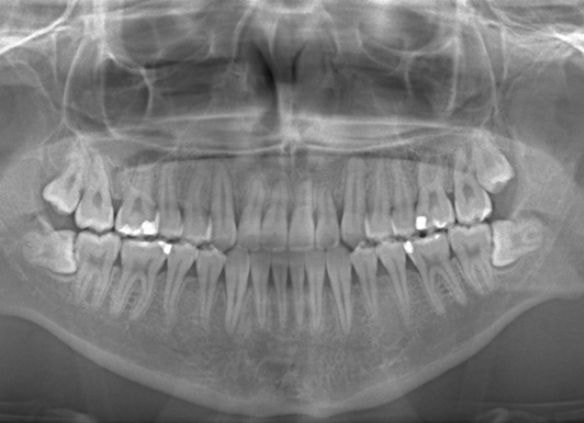

治療前

やはり統計通り、左上3番の埋伏です。

左上2番の歯根吸収が認められますが、保存不可能なレベルではありません。

成人の反対咬合なので、少し顎関節にダメージはありますが、重症ではありません。